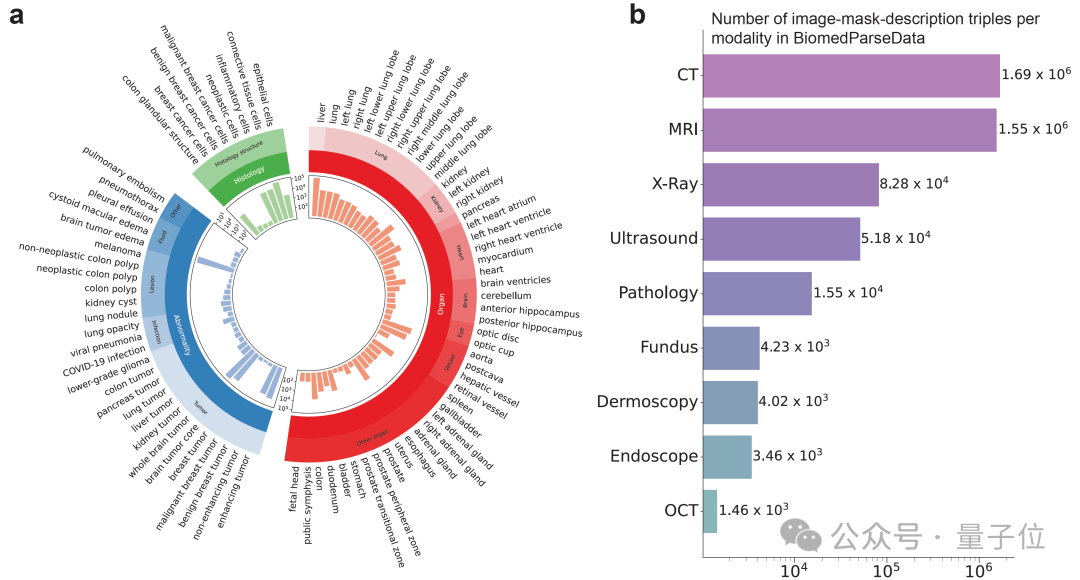

为支持BiomedParse的预训练,研究团队利用GPT-4从45个公开的医学图像分割数据集生成了首个覆盖对象识别、检测和分割任务的数据集BiomedParseData。

该数据集包含超过600万个图像、分割标注与文字描述三元组,涵盖64种主要生物医学对象类型及82个细分类别,涉及CT、MRI、病理切片等九种成像模式。